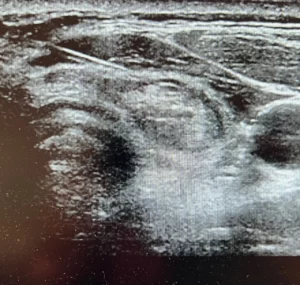

La technique TOETVA permet de réaliser une opération de la thyroïde sans cicatrice visible au niveau du cou. Cette approche mini-invasive est proposée dans des indications bien sélectionnées, avec un objectif à la fois médical, fonctionnel et esthétique.